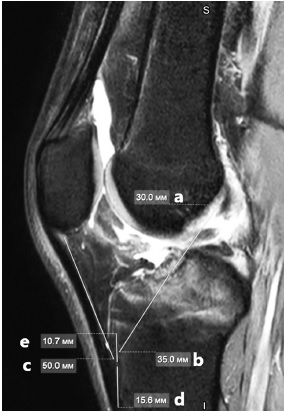

При этом на предоперационных сагиттальных срезах МРТ, проходящих в плоскости межмыщелкового пространства, определяют предполагаемую длину поврежденной ПКС путем измерения расстояния между точками ее анатомического прикрепления на латеральном мыщелке бедренной и медиальном мыщелке большеберцовой костей, предполагаемую длину костного тоннеля в большеберцовой кости, длину сухожильной части связки надколенника, длину дистальной части блока большеберцовой кости, которая является продолжением связки надколенника, а также потенциальную длину проксимальной части костного блока большеберцовой кости (рис. 3). Возможности МРТ в качестве инструмента измерений анатомических структур коленного сустава изложены в работе S. Sundar с соавторами [11].

Рис. 3. МРТ-измерения: предполагаемая длина поврежденной передней крестообразной связки (a), предполагаемая длина костного тоннеля в большеберцовой кости (b), длина сухожильной части связки надколенника (c), длина дистальной части блока большеберцовой кости (d), длина проксимальной части костного блока большеберцовой кости (e)

Fig. 3. MRI-measurments: the approximate ACL length (a), the approximate tibial tunnel length (b), patella tendon legth (c), distal tibial bone block length (d), proximal tibial bone block length (e)

Таким образом, сумма длин a и b будет равняться сумме длин c и d (a+b = c+d). В то же время сумма длин d и e должна составлять не менее 25,0 мм, что соответствует длине интерферентного винта.

После проведенных измерений выполняют распил костного блока большеберцовой кости таким образом, чтобы вся его часть располагалась в костном тоннеле большеберцовой кости. При этом интраоперационно определялось начало зоны прикрепления связки надколенника, от которой в проксимальном направлении выполнялся распил большеберцового блока в соответствии с предоперационными измерениями. Аналогично выполнялся распил в дистальном направлении. Например, при предполагаемой длине ПКС 30 мм, канала большеберцовой кости — 35 мм и длине собственной связки надколенника — 50 мм распил большеберцовой кости будет выполнен таким образом, чтобы его дистальная часть составляла не менее 15 мм, а проксимальная — не менее 10 мм (рис. 4).